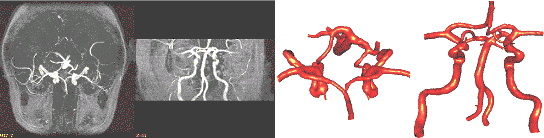

3.3. Circle of Willis

The region growing segmentation approach was applied to

the construction of realistic anatomical models of the circle

of Willis from 3D MRA images. The MIPs of the anatomical

images before and after applying the region growing procedure

are shown in Fig. 5a and 5b, respectively. The reconstructed

model after smoothing and optimization is shown in Fig.

5c.

a)

b) c)

Figure 5. Reconstruction

of the circle of Willis from MRA images: a) MIP of original

images; b) MIP after region growing; c) reconstructed surface

model.

a) b)

Figure 6. Finite element

grid of the circle of Willis: a) final geometrical model

after cutting arterial branches;

b) surface of the final finite element grid with uniform

element size distribution.

The final geometrical model after cutting several arterial

branches along contours of geodesic distances is shown in

Fig. 6a. This model was then used to generate a finite element

grid with uniform element size distribution. The final mesh

(Fig. 6b) contained approximately 4 million elements.

A second case illustrates the use of adaptive background

grids to specify an element size distribution that depends

on the local surface curvature. Fig. 7a and 7b show the

MIP of the MRA images from two different viewpoints. The

reconstructed model is shown from similar viewpoints in

Fig. 7c and 7d.

c) d)

Figure 7. Circle of

Willis model reconstructed from MRA images: a) and b) MIP

projections from different viewpoints; c) and d) reconstructed

model from similar viewpoints.

A close-up view of the triangulation of the final model

is shown in Fig. 8a. This triangulation was then used to

refine an adaptive background grid based on its local curvature

in order to specify an element size distribution that yields

roughly the same number of elements across any cross-section

of the model. The generated finite element grid (Fig. 8b)

contained approximately 1 million elements.